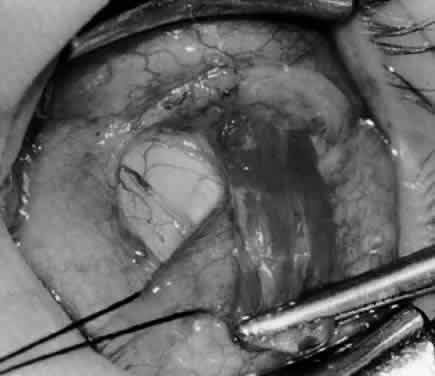

Fig. 9. A Westcott scissor is used to dissect the intermuscular septum and expose the insertion of the inferior oblique muscle.

Fig. 10. The inferior oblique muscle is placed on the Green muscle hook. The exposed insertion is ready for myotomy, myectomy, disinsertion, placement of sutures for recession, or removal for the extirpation procedure.